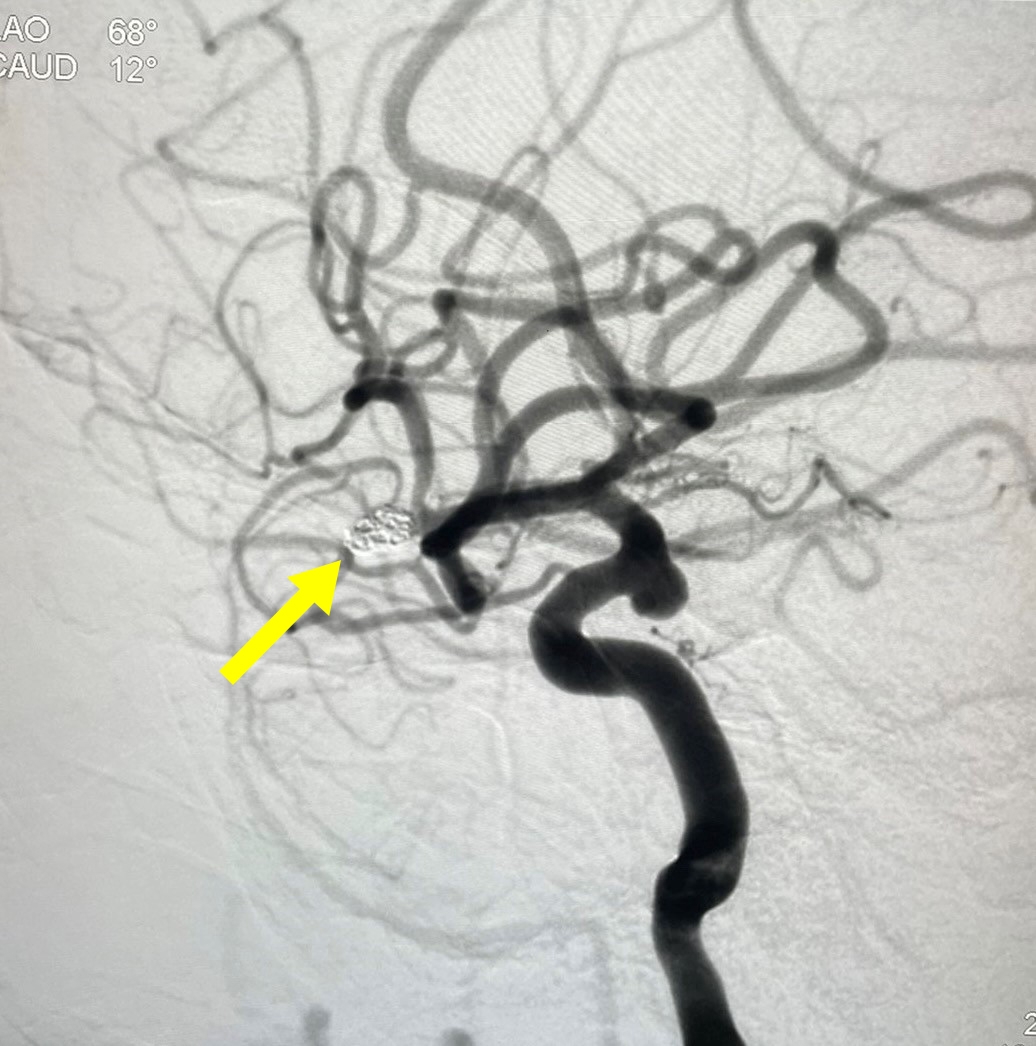

![]() |

| Vị trí của túi phình sau can thiệp |

Kết quả sau hơn một giờ đồng hồ thủ thuật, các bác sĩ đã can thiệp thành công, túi phình đã được nút tắc hoàn toàn. ThS.BS Nguyễn Quốc Thái cho biết, sau can thiệp, bệnh nhân tỉnh táo, trả lời đúng y lệnh, không yếu liệt, giảm đau đầu và bệnh nhân đang hồi phục tốt.